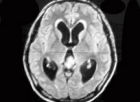

真菌性腦膜炎真菌性腦膜炎多呈腦脊液單個核細胞增多,一般為(20~500)×106/L。多核白細胞比例往往不固定,但多在50%以下,而某些真菌性腦膜炎可表現為腦脊液呈多核白細胞增多為主,這大多見於麴黴菌、接合菌綱、芽生菌屬感染。嗜酸性細胞增多性腦膜炎則提示球孢子菌感染的可能。

在長期套用大劑量糖皮質激素的患者以及愛滋病患者等嚴重免疫缺損者中,即使是在隱球菌腦膜炎活動期也可呈腦脊液細胞數極低甚至正常。這種表現與大劑量套用可的松的小鼠隱球菌腦膜炎模型相似。雖然絕大多數真菌性腦膜炎呈單個核細胞增多性腦膜炎,但在慢性腦膜炎中可出現中性粒細胞增多性腦脊液表現。